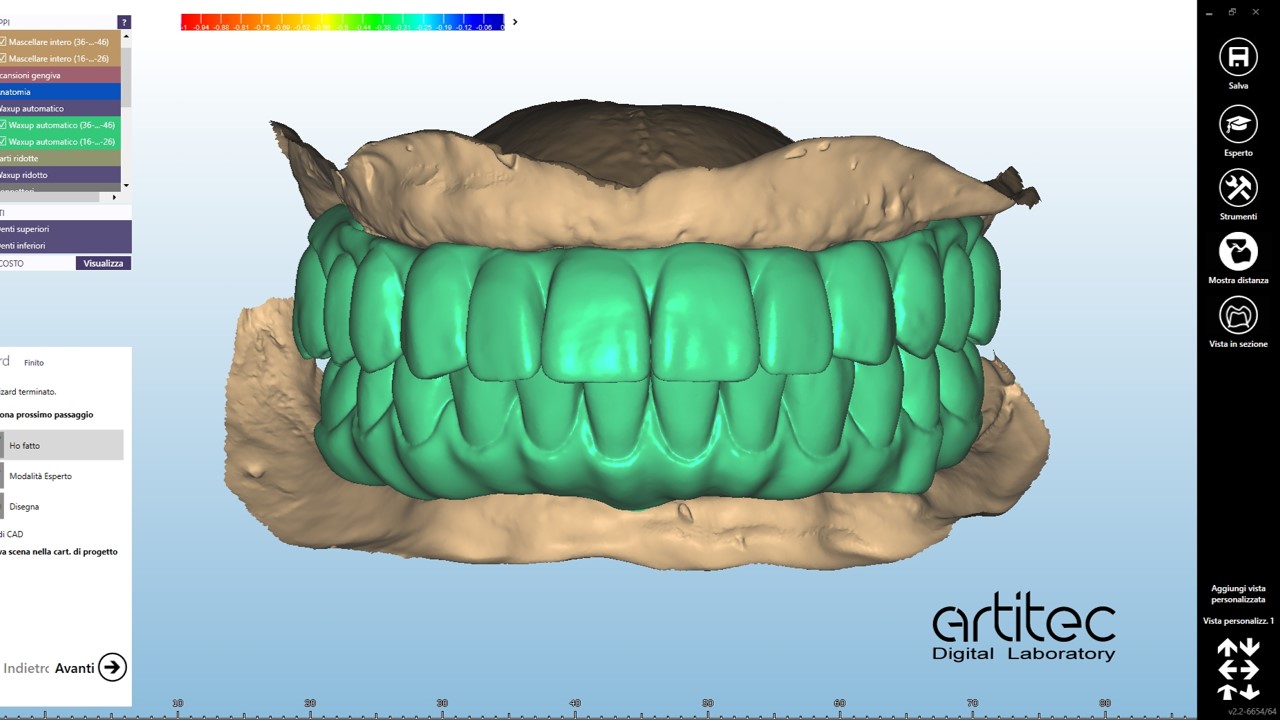

foto 01 digital previsualizzazione software

foto 02 digital previsualizzazione software

foto 03 digital previsualizzazione software

foto 04 digital previsualizzazione software

foto 05 digital previsualizzazione software

foto 15 progetto protesico ultimato